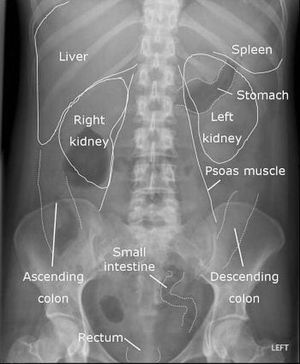

Anatomy

In xray

Mbbs

Medicalstudent